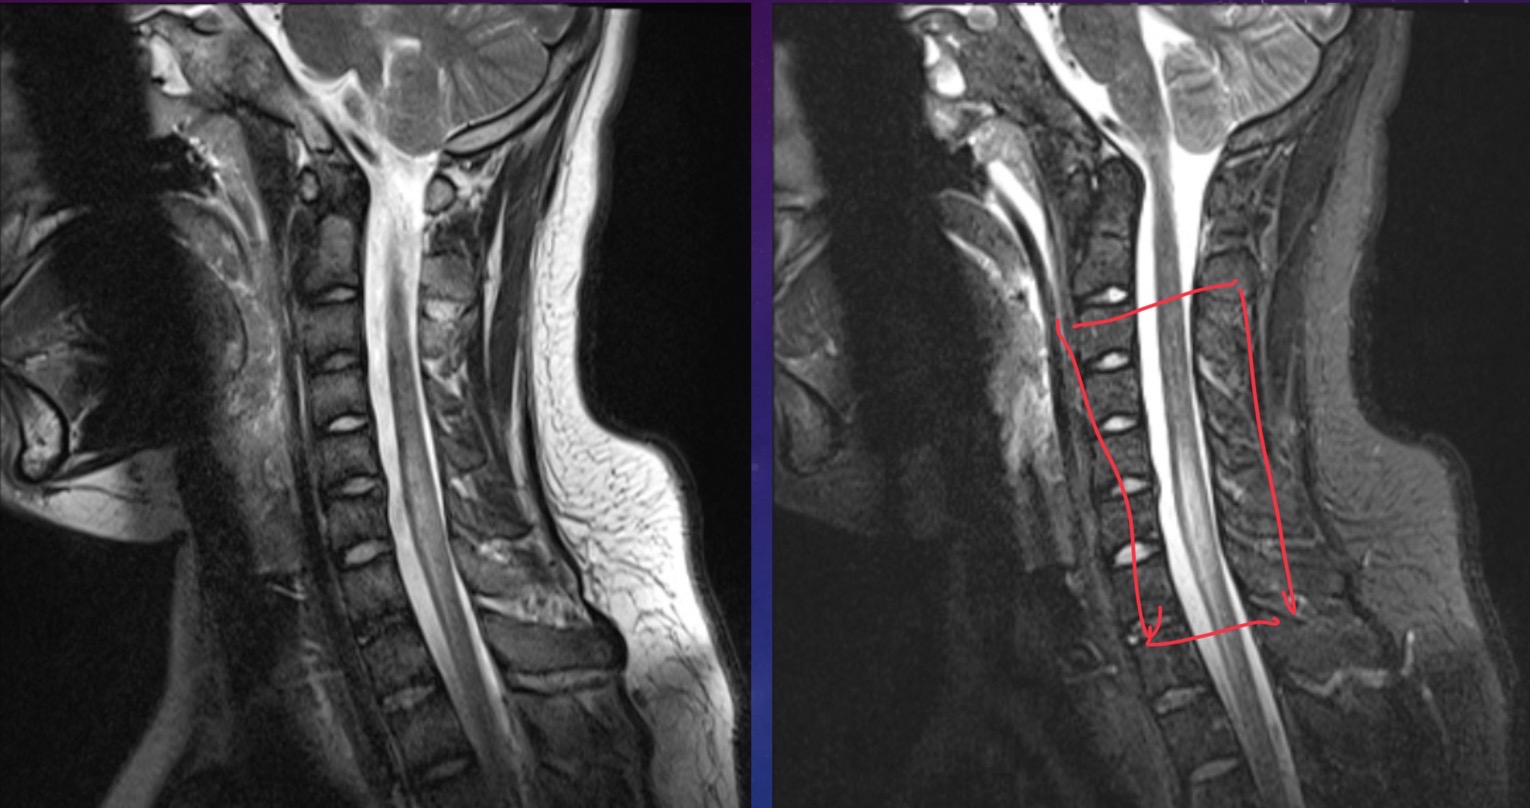

12-year-old male is a secondary school student with acute onset tetraparesis. He has a rapid ascending paralysis with neuromuscular weakness with brisk reflexes. Patient also has cervical myelitis

Cervical transverse myelitis. Canal looks narrower and bulges forward